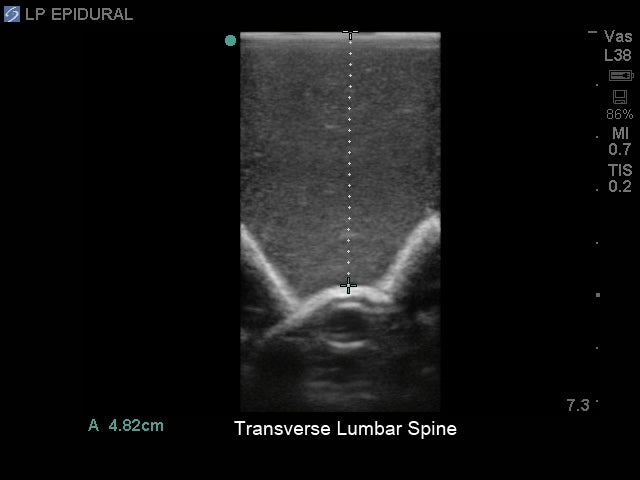

The lumbar puncture and lumbar epidural tissue insert is constructed using Blue Phantom self-healing and ultra-durable tissue. Our durability provides you with better training at a better cost. Our patented tissue is superb in ultrasound imaging characteristics and provides the same tactile feedback as real human tissue. With your Blue Phantom training model and the ultrasound system of your choice, you can expect the same level of quality experienced imaging patients in a clinical environment. Blue Phantom lumbar puncture and lumbar epidural replacement insert will perform optimally using any ultrasound imaging system configured with the appropriate ultrasound transducer.

- Ultrasound can be used for identification of the optimal insertion points, angle of needle insertion, and determination of the depth to the ligamentum flavum, epidural space, and spinal cistern